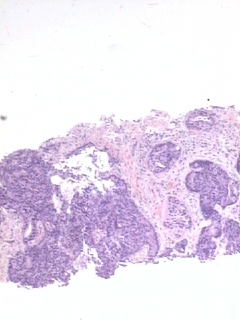

- Figure 2 a- Gleason 4 - Caso 20 HE-40x.JPG

- Figure 2 b- Gleason 4 - Caso 20 HE-100x.JPG

- Figure 2 c- Gleason 4 - Caso 20 HE-200x.JPG